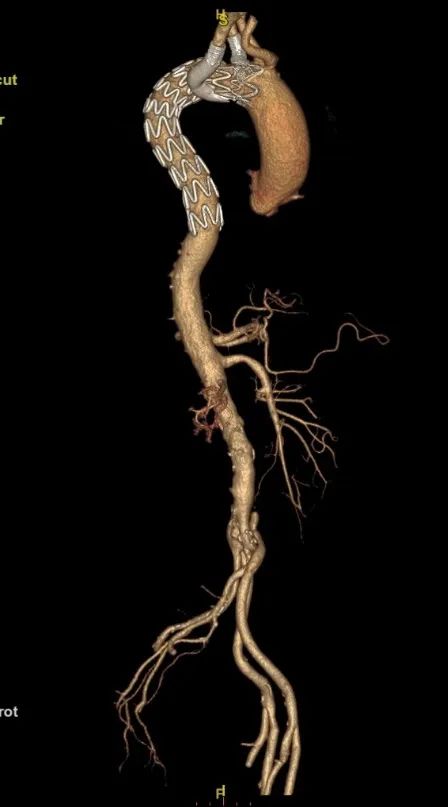

患者,女,72岁。

诊断:主动脉夹层,壁间血肿。

手术方案:TEVAR+右侧和左侧锁骨下烟囱。

手术结果良好,无任何内漏。